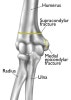

과상부 골절(Supracondylar fracture) : 팔을 쭉 펴고 손을 짚으면서 넘어지고 과상부가 부러졌어요

소아에서 가장 흔한 골절로 소아 주관절 부위의 골절의 55~80%를 차지하지만 성인에서는 드뭅니다.

원위 골편의 위치에 따라 신전형과 굴곡형으로 나눕니다.

- Extension type : 원위 골편이 근위 골보다 후방에 위치. 훨씬 흔합니다.

2. Flexion type : 원위 골편이 전방에 위치. 전체 과상부 골절의 2~4% 차지합니다.